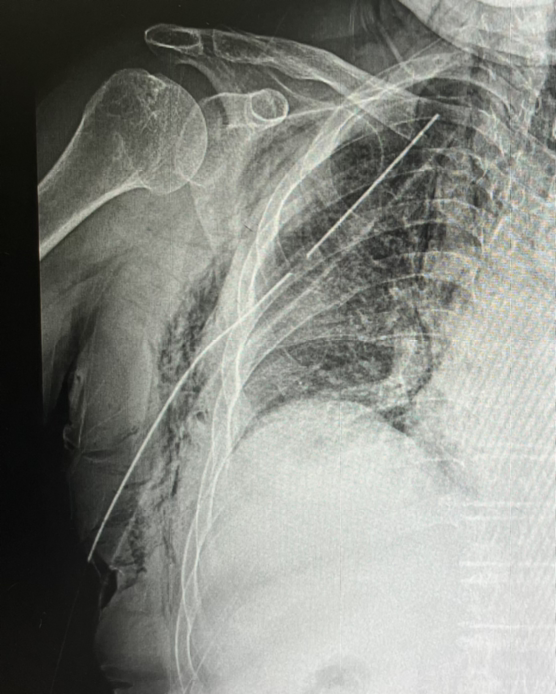

쇄골과 늑골이 부러진

할머니를 맞이하였다.

흉부 CT 사진에서

기흉과 피하기종이 보여서

모처럼 흉관을 삽입하였다.